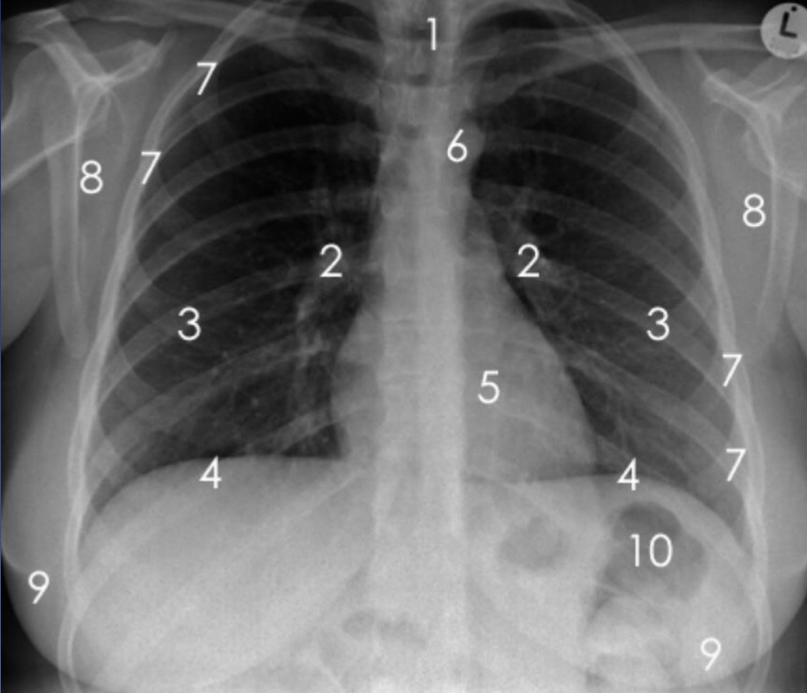

Identify the following anatomical structures